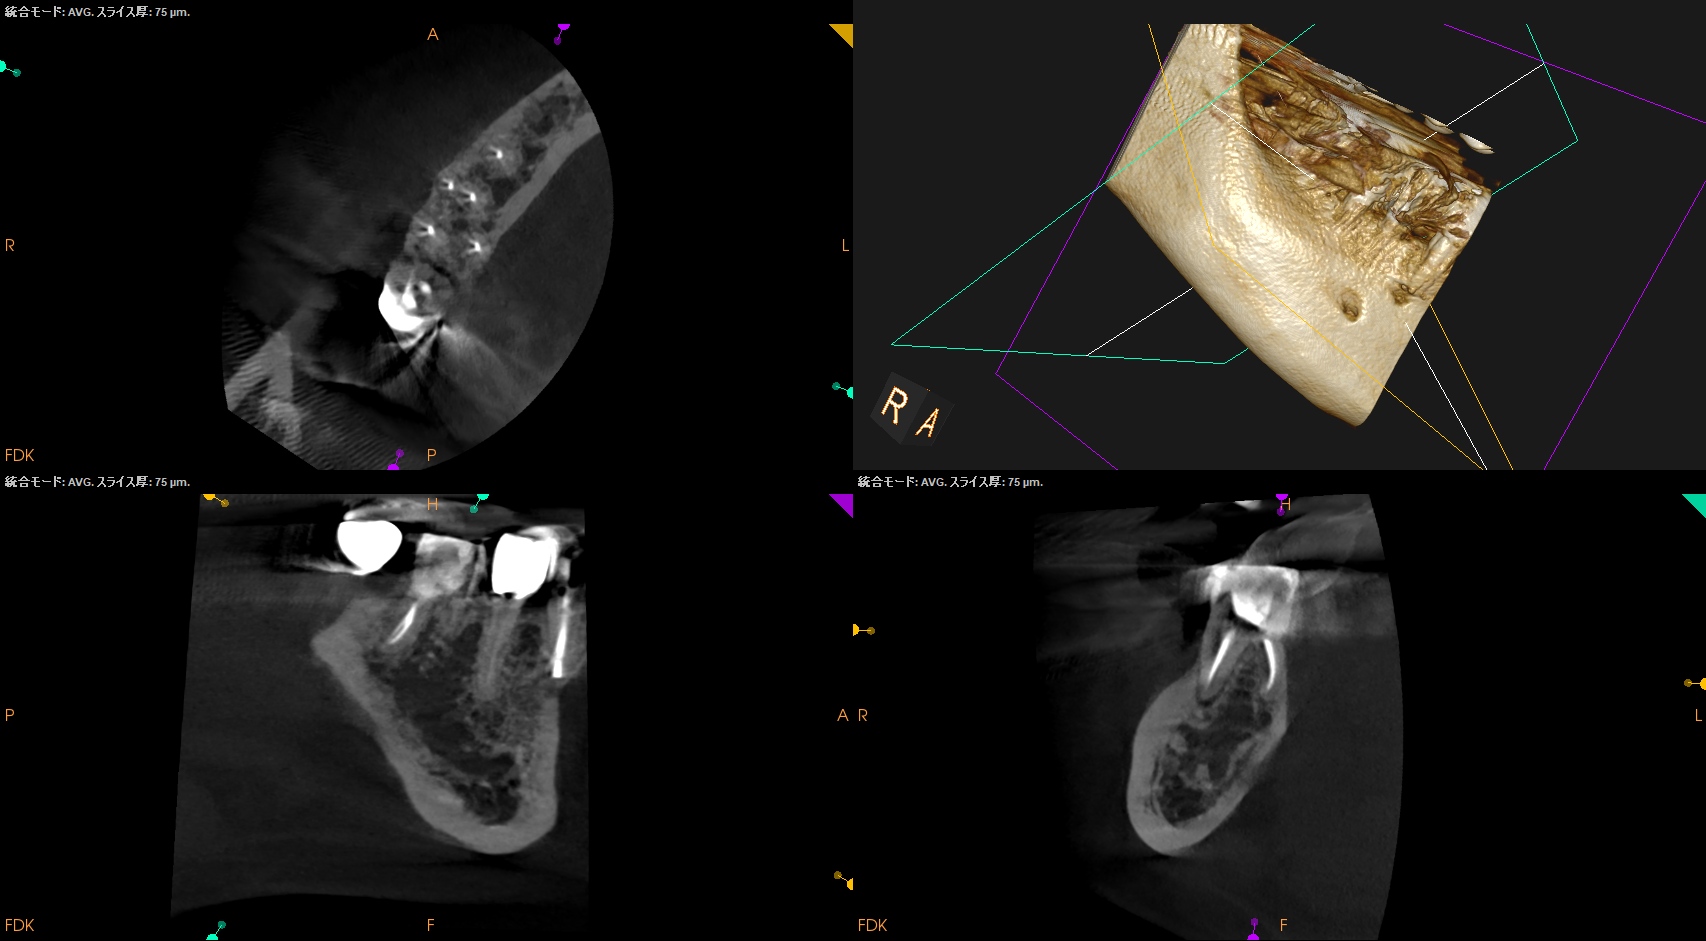

術後にPA, CBCTを撮影した。

MB

ML

D

Radix

ということで問題ないだろう。